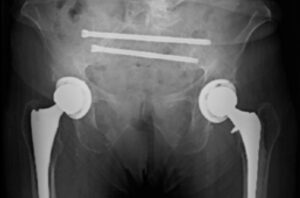

Dr. Robert Eastlack uses bilateral iFuse 3DTM implants in the Bedrock trajectory to supplement spinopelvic fixation and provide permanent SI joint stabilization and fusion.